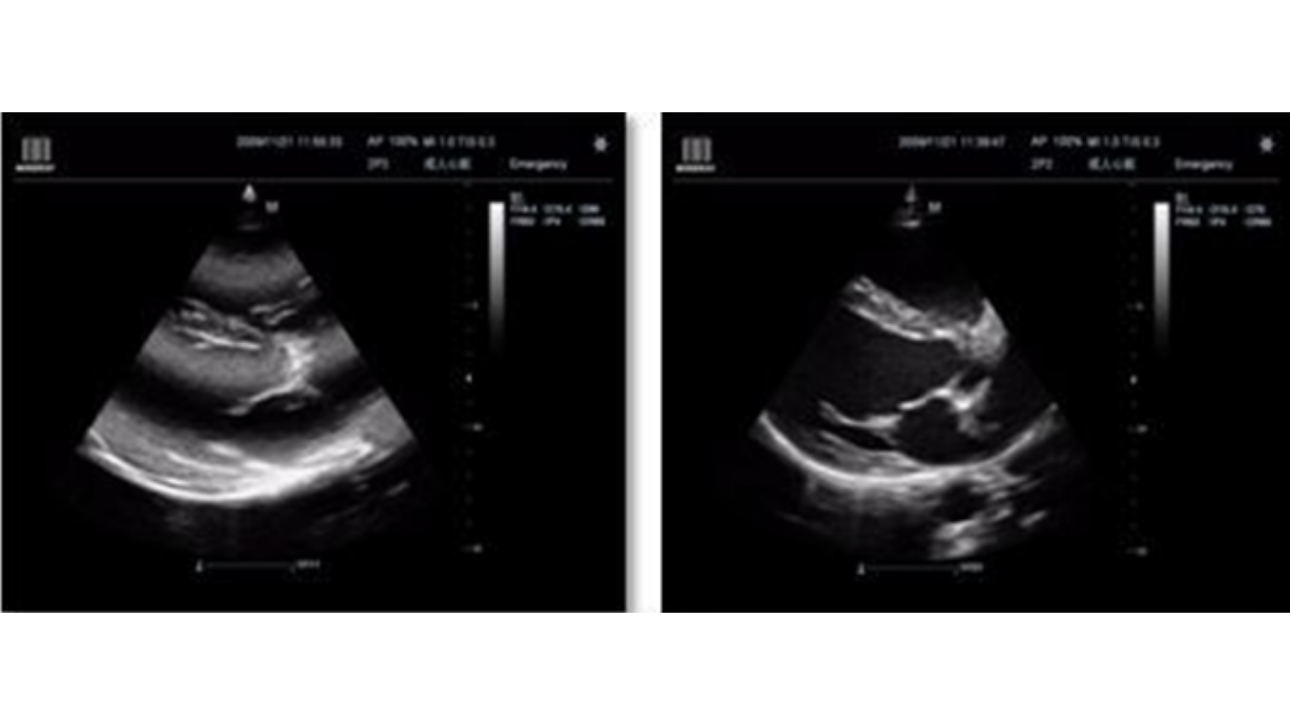

Clinical Images

• p50-s6-1-web

L12-4s iNeedle

• p50-s6-2-web

Brachial Plexus

• p50-s6-3-web

Subscapalaris tendon

• p50-s6-4-web

Long Axis

• p50-s6-5-web

Free Xros